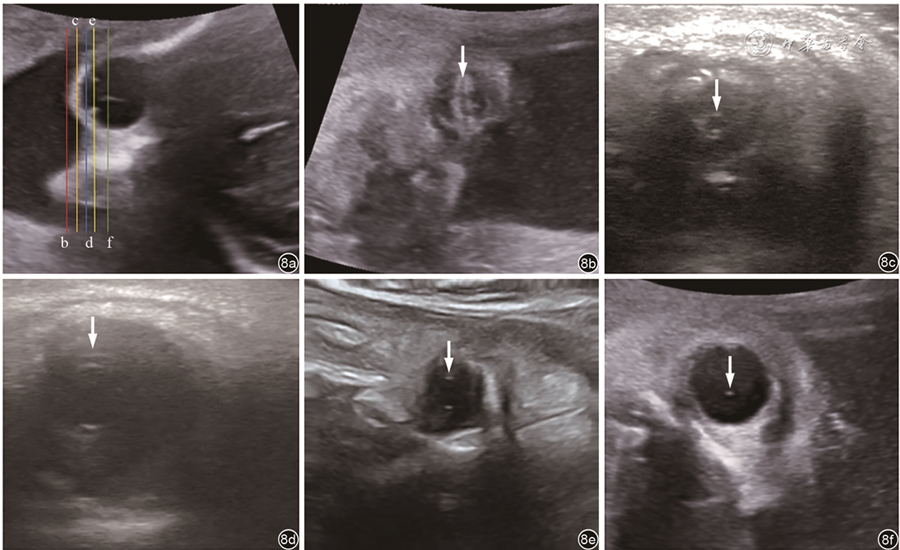

在显示面额冠状切面后,将声束平面继续缓慢向后平移,可以观察到一系列的胎儿眼球冠状切面。从前往后可观察眼睑及眼裂、瞳孔、睫状环、晶状体环和玻璃体动脉(部分孕周)(图8)。

图8 胎儿眼冠状切面超声声像图。图a为颞侧的眼球横切面,彩色线条为b~f切面的对应的切面位置,图b~f分别为眼睑和眼裂切面、瞳孔切面、睫状环切面、晶状体切面和玻璃体及玻璃体动脉切面,箭头所指分别为眼睑和眼裂、瞳孔、睫状环、晶状体和玻璃体动脉